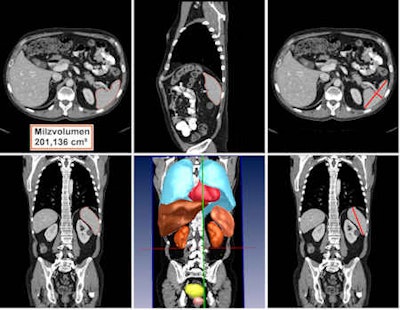

The Theseus-Medico computer-aided detection (CAD) software was developed using machine learning methods, including a probabilistic boosting tree, marginal space learning, and 3D Haar-like feature algorithms. It can complete automated volumetry of the spleen in about 15 seconds, Hammon noted.

To test the software, the researchers performed a retrospective analysis on the CT scans of 15 consecutive patients with malignant lymphoma. An experienced radiologist also determined the estimated splenic volume and performed manual volume segmentation on the three consecutive CT scans for each patient.

Manual volumetry was used as the gold standard. Estimated splenic volumetry (splenic index) was calculated by using the equation of 30 cm3 + 0.58 (width x length x thickness). Automated volumetry was performed without any problems in all CT datasets within 15.2 seconds (± 2.4 seconds), Hammon said.

Average splenic volume:

- Automated volumetry: 268.21 cm3

- Manual volume segmentation: 281.58 cm3

- Estimated volume determination: 268.93 cm3

Correlation coefficients:

- Automated volumetry and manual volume segmentation: 0.99

- Manual volume segmentation and estimated volume segmentation: 0.91

- Automated volumetry and estimated volume segmentation: 0.91

Excellent correlation was also found tracking changes in splenic volume over two consecutive time points, with coefficients of 0.95 (automated volumetry and manual volume segmentation), 0.95 (manual volume segmentation and estimated volume segmentation), and 0.91 (automated volumetry and manual volume segmentation). All correlation values were statistically significant.